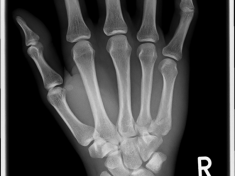

Röntgenbilder